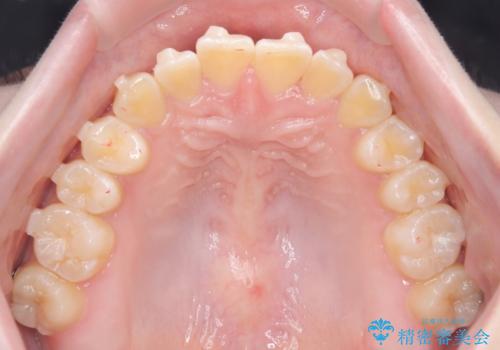

【インビザライン】オープンバイト。凸凹を治したい

- オープンバイトを主訴に来院されました。

インビザラインを用いIPRと遠心移動を行いオープンバイトと叢生の改善を行なっております。

前歯の叢生がわずかにありますが、追加アライナーの作成は希望されなかったため、歯を動かしていく動的治療は終了となりました。